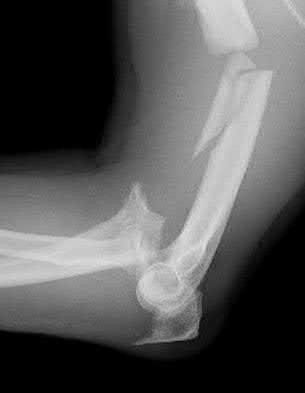

A 51-year-old carpenter presents with a distal humerus nonunion (Figures A and B). After repair of the nonunion, he is lost to follow up for 3 months and then presents to your clinic pain-free and with evidence of fracture union. On examination the elbow arc of motion is 10-80 degrees. Following a brief failed trial of conservative management, you recommend:

Limited flexion outside a functional range of motion (30-130 degrees) can be quite debilitating, and it is often addressed with open release of the posterior bundle of the MCL and posterior capsule and excision of osteophytes.

A frequent complication of distal humerus fractures is post-traumatic stiffness. This patient has had multiple procedures about the distal humerus, and the question stem implies that he did not complete a structured range of motion protocol following the repair of his nonunion. Beyond a trial of conservative management, there are many techniques described for capsule and soft tissue releases as well as bony resections if heterotopic ossification is present. This patient's severely limited flexion would best be addressed with a release of the posterior bundle of the MCL, and with flexion